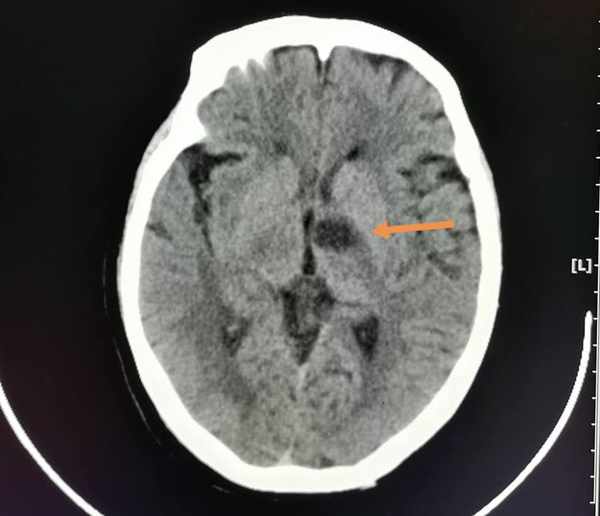

像這位69歲老太太,頭疼、右側肢體發麻無力,急診CT排除了腦出血,同時發現左側丘腦和內囊密度略减低,提示腦梗死。

5天后複查,更典型了:

這種小範圍腦梗死(腔隙性腦梗死),治療效果一般都很好。